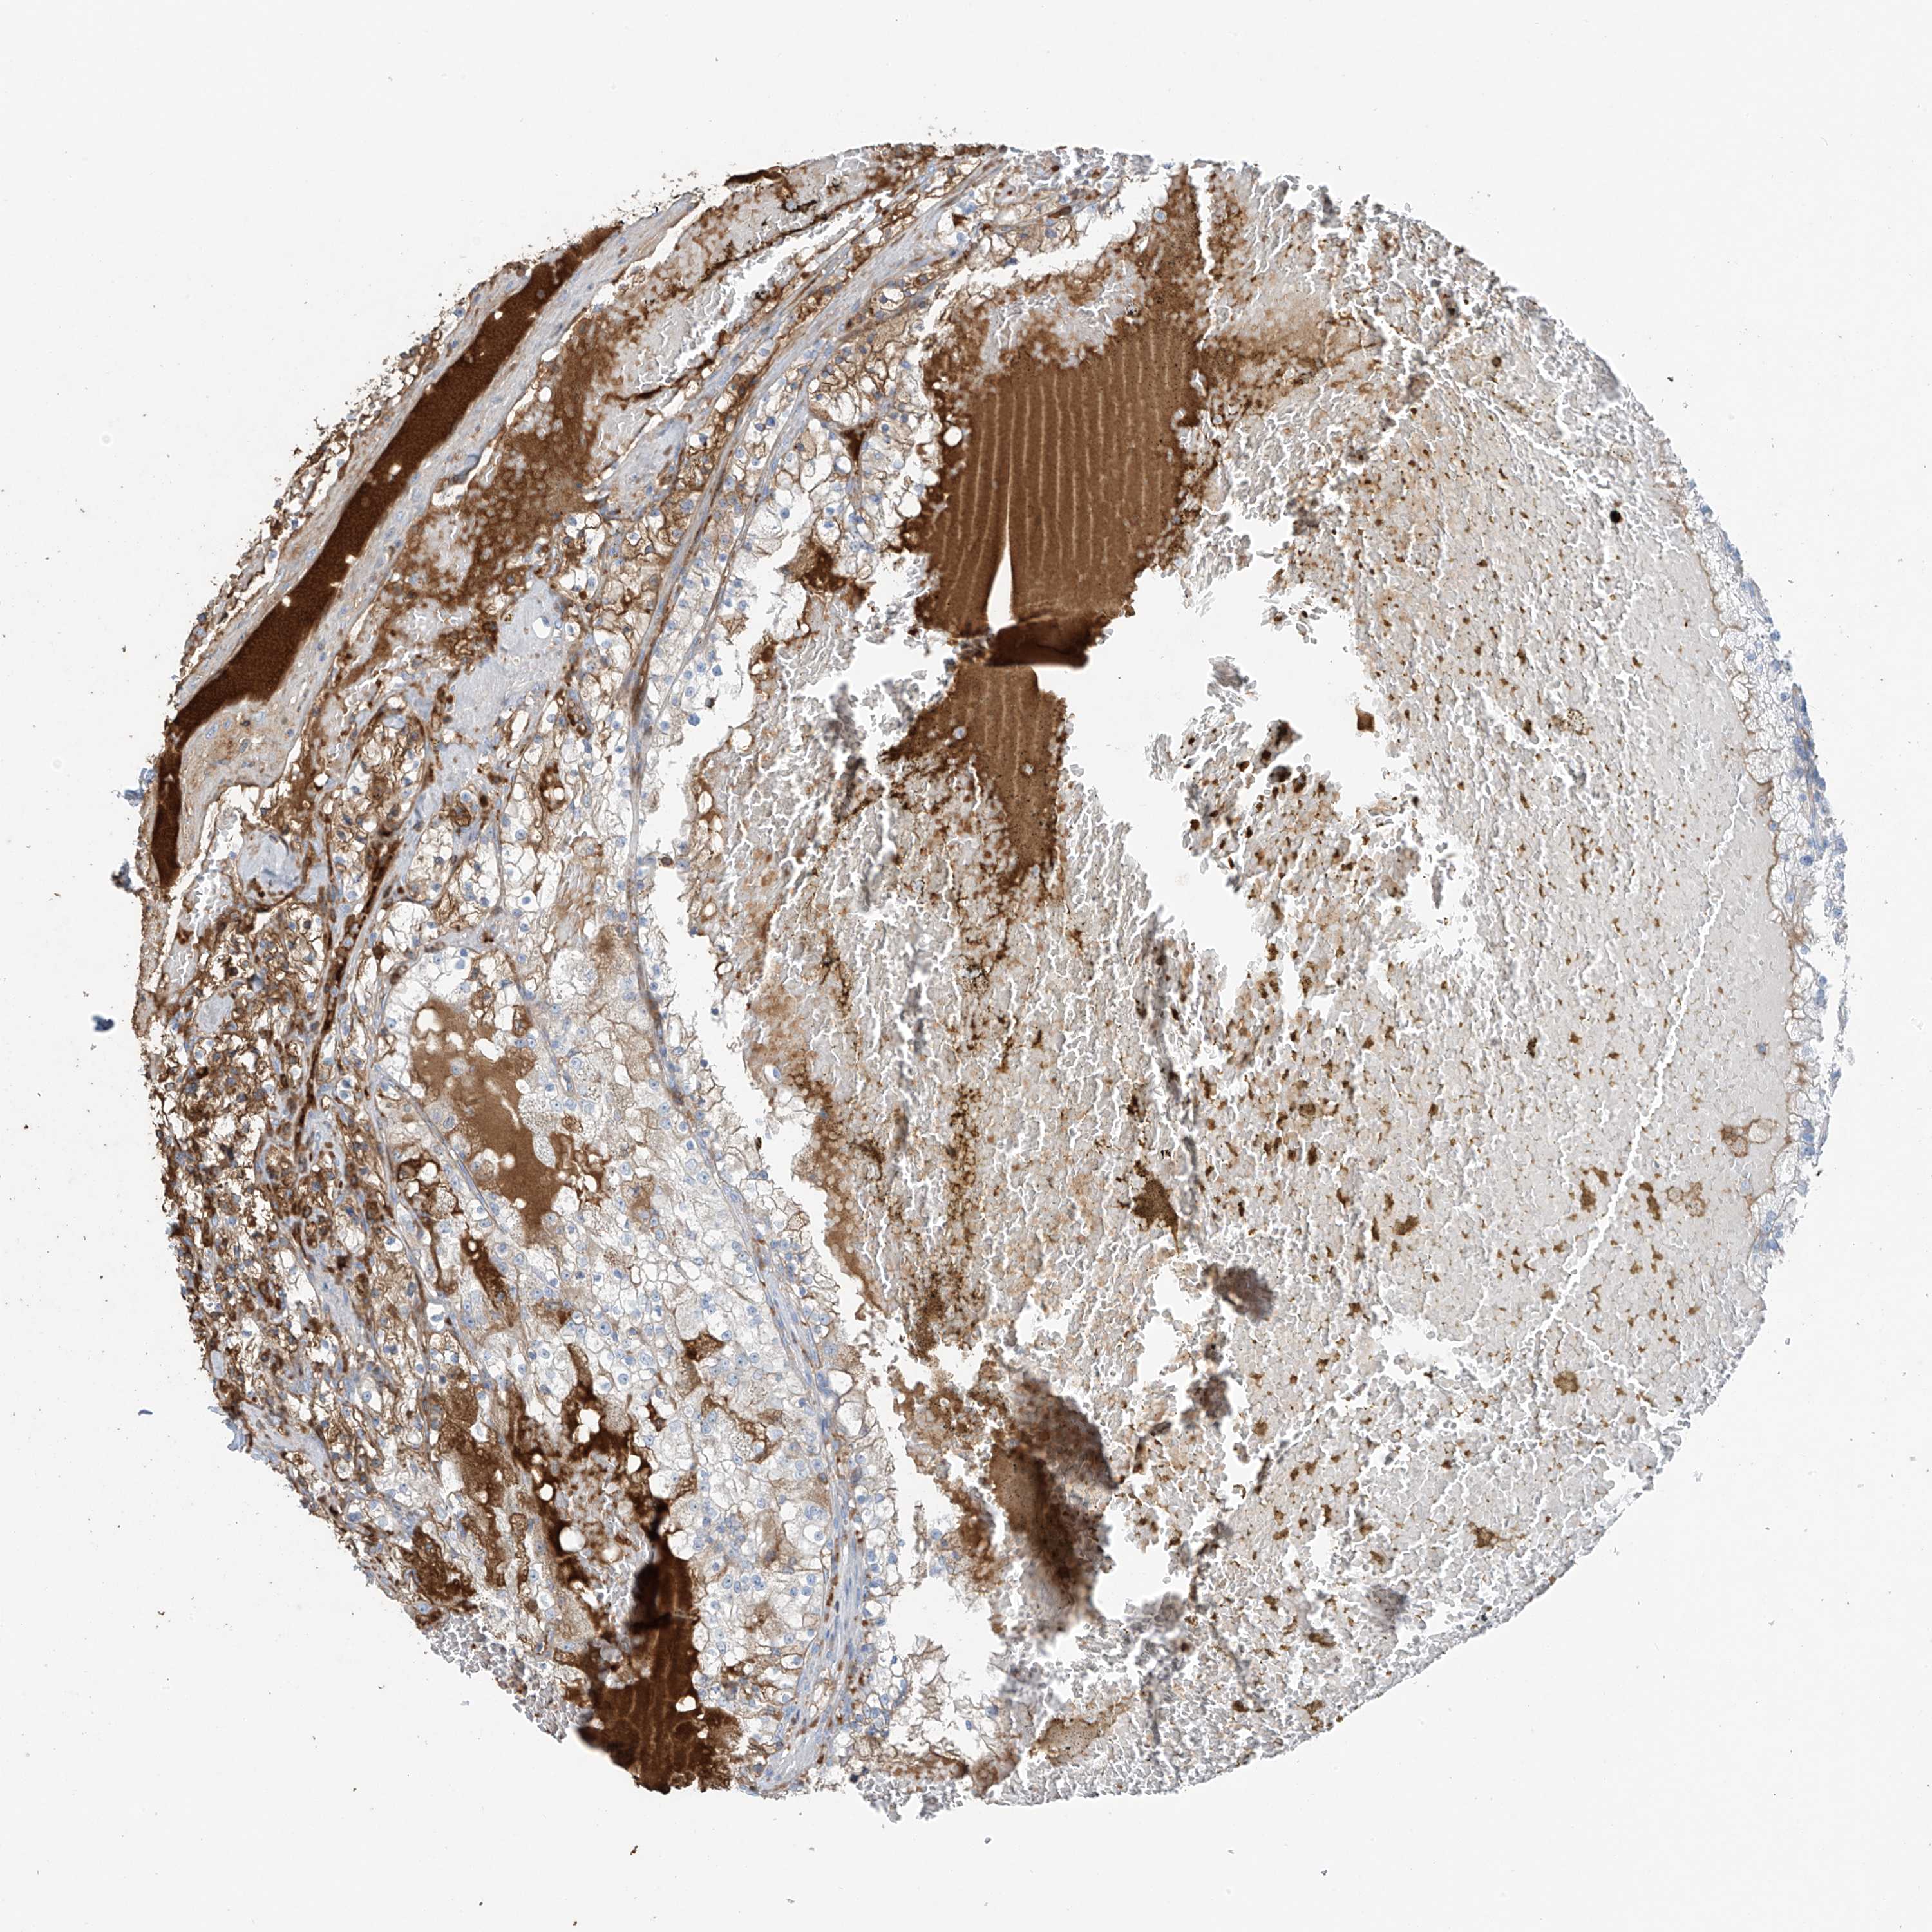

KIDNEY RENAL CLEAR CELL CARCINOMA (VALIDATION) - Interactive survival scatter ploti

The Survival Scatter plot shows the clinical status (i.e. dead or alive) for all individuals in the patient cohort, based on the same data that underlies the corresponding Kaplan-Meier plots. Patients that are alive at last time for follow-up are shown in blue and patients who have died during the study are shown in red.

The x-axis shows the expression levels (FPKM) of the investigated gene in the tumor tissue at the time of diagnosis. The y-axis shows the follow-up time after diagnosis (years). Both axes are complimented with kernel density curves demonstrating the data density over the axes. The top density plot shows the expression levels (FPKM) distribution among dead (red) and alive patients (blue). The right density plot shows the data density of the survived years of dead patients with high and low expression levels respectively, stratified using the cutoff indicated by the vertical dashed line through the Survival Scatter plot. This cutoff is automatically defined based on the FPKM cutoff that minimizes the p-score. The cutoff can be changed by dragging the vertical line or by entering a cutoff value in the square labeled "Current cut-off".

Under the Survival Scatter plot the p-score landscape (black curve; left axis) is shown together with dead median separation (red curve; right axis). Dead median separation is the difference in median mRNA expression between patients who have died with high and low expression, respectively. It is calculated as follows: median FPKM expression of dead patients with high expression - median FPKM expression of dead patients with low expression. This is intended to aid the user in visually exploring custom cutoffs and the associated p-scores and dead median separation.

Individual patient data is displayed and can be filtered by clicking on one or more of the category buttons on the top of the page. Categories describing expression level and patient information include: high, low, alive, dead, female, male and tumor stages. The scale of the x-axis can be toggled between linear and log-scale by clicking on the "x log" button. Mouse-over function shows TCGA ID, patient information and mRNA expression (FPKM) for each patient.

& Survival analysisi

Kaplan-Meier plots summarize results from analysis of correlation between mRNA expression level and patient survival. Patients were divided based on level of expression into one of the two groups "low" (under cut off) or "high" (over cut off). X-axis shows time for survival (years) and y-axis shows the probability of survival, where 1.0 corresponds to 100 percent.

PDGFC is validated prognostic, high expression is favorable in Kidney Renal Clear Cell Carcinoma (validation)

: 6.46

Average pTPM 7.6

Number of samples 100